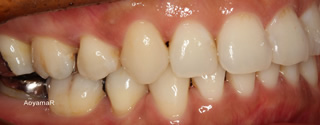

そう生(歯並びのガタガタ、乱杭歯、八重歯)の矯正症例

CASE 17

(38歳 女性 )

上下第一小臼歯抜歯による叢生改善

マウスピース型カスタムメイド矯正装置(インビザライン)単独による治療

治療後